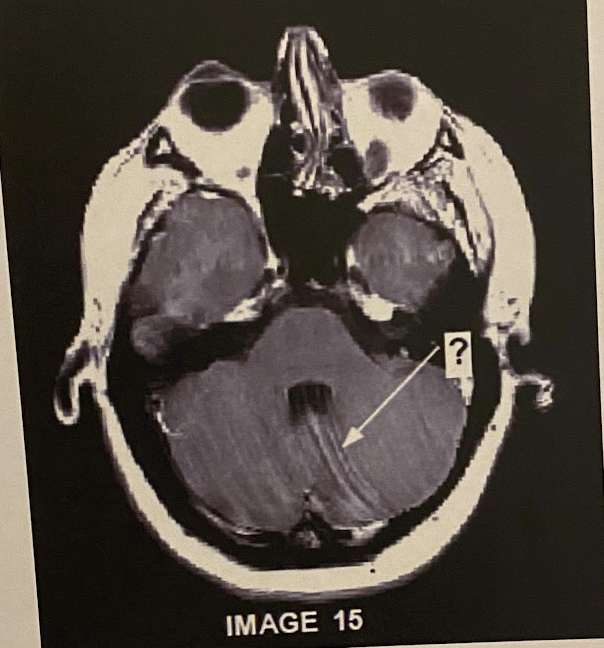

Q

The artefact demonstrated in this image represents truncation. True or False

A

a) true

Fix this by increasing the matrix to decrease the chance of truncation/Gibbs/ringing or psuedosyrnix